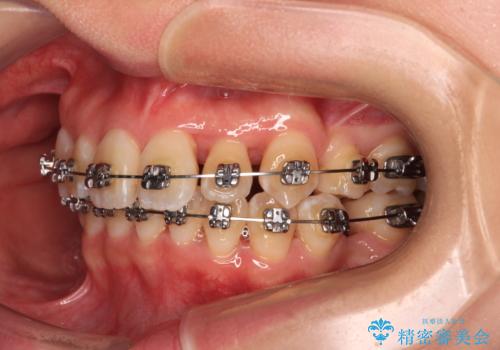

- 矯正装置

- メタルブラケット

- 3年3ヶ月

- 治療回数

- 30回以上

奥歯の咬み合わせ改善にはどうしても長期間を要します。

3年強とお伝えしておりましたが、予想通り3年3ヶ月で治療を終えることができました。